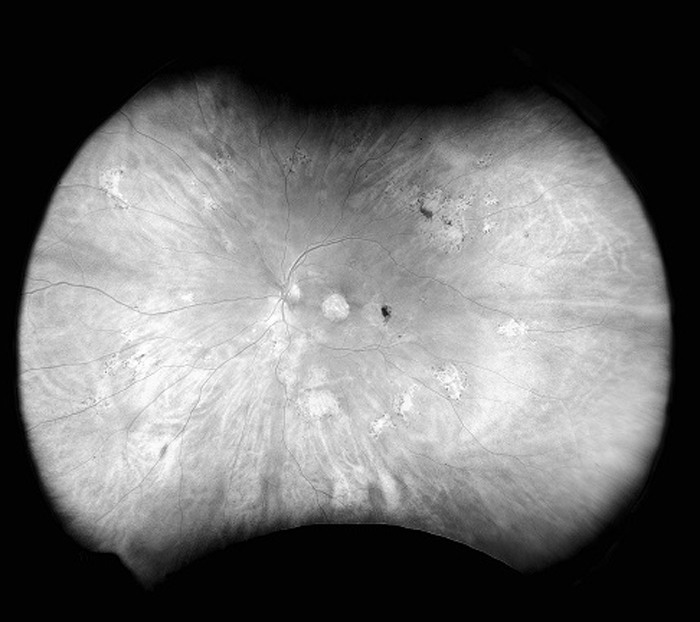

Monaco est une nouvelle approche intéressante pour améliorer votre examen clinique. Seul appareil d’imagerie de la rétine ultra-grand champ à posséder un SD-OCT intégré, Monaco produit une image optomap® à 200° en une seule prise en moins d’½ seconde ainsi que des vues transversales OCT à 40° des structures de la rétine. Monaco permet d’obtenir rapidement une image en plusieurs modalités avec balayages couleur, autofluorescence et OCT, pour les deux yeux, en seulement 90 secondes.

- Les images optomap et les balayages OCT sont corrélés afin de faciliter l’examen des pathologies.

- Les images Couleur, AF et OCT sont présentées ensemble dans une même vue.